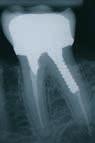

ÅR EN RODBEHANDLET TAND har nået et punkt, hvor tandsubstansen er stærkt reduceret pga. cuspisfraktur, caries, fyldninger eller som følge af endodontisk behandling (Fig. 1A og B), kan det være indiceret, at tanden genopbygges med stift, opbygning samt støbt restaurering (1-5). Førstnævnte for at opnå tilstrækkelig retention af opbygningen. Det er udbredt, at guttaperkafjernelse er mekanisk baseret med anvendelse af et roterende bor (Fig. 1C) (3,6). Boret placeres over rodfyldningen, hvorefter den koronale del samt noget af rodkanalvæggen fjernes mekanisk (4). Den mest apikale del af rodfyldningen bibeholdes, for at denne fortsat er tæt (2,3). En af udfordringerne ved en optimal guttaperkafjernelse samt stiftudboring er muligheden for at følge rodfyldningen uden at afvige fra rodkanalen (7,8). Perforation af tandroden kan ske ved ukorrekt vinkling (Fig. 1C og D), og risikoen forstærkes yderligere ved kraftigt reduceret tandsubstans i den cervikale del af kronen (9,10). Inspektion og belysning kan være besværliggjort, og endelig kan rodfyldningen være meget hård, hvilket komplicerer den taktile sansning under præparationen (9,11). Den utilsigtede vinkling af stiftudboringen, ultimativt rodperforationen,

Fig. 1. Radiologisk sekvens efter en rodperforation i forbindelse med en stiftpræparation i en underkæbemolar (-6). A. Røntgenbillede før rodbehandling. Rodkanalmorfologien viser, at den distale rod har to adskilte rodkanaler (pil). B. Rodbehandling afsluttet og kontrolleret. C. Initial mekanisk fjernelse af rodfyldning. D. Efter mekanisk fjernelse af rodfyldning ses en retningsafvigelse i forhold til den nederst beliggende rodfyldning. E. En midlertidig fyldning af rodkanalen viser rodperforationen (pil). Der er indhentet patientsamtykke til visning af røntgenbilleder.

Fig. 1. Radiologic sequence after root perforation in connection with mechanical preparation of a post in a mandibular molar (-6). A. Radiograph before the procedure. The morphology of the root canal shows that the distal root has two separate root canals (arrow). B. Procedure completed and controlled. C. Initial mechanical removal of root filling. D. After the mechanical removal of root filling the direction of the drill deviates from the lowest part of the root filling. E. A temporary filling of the root canal shows the root perforation (arrow). The pictures are used with the permission and consent of the patient.

kan forekomme for selv en erfaren tandlæge, da sågar et optimalt 2D-røntgenbillede ikke altid gengiver korrekt morfologi (11,12).